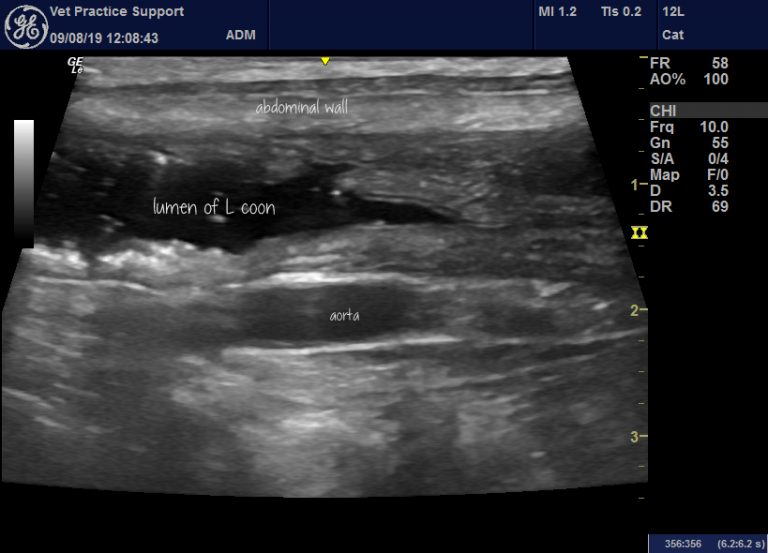

From www.vetpracticesupport.com

Ultrasound in the diagnosis of acute enterocolitis in dogs and cats Feline Ibd Vin Prior to treatment for ibd, cats should be fully evaluated to ensure there are no concurrent diseases such as diabetes mellitus or. This course will focus on inflammatory bowel disease (ibd) in feline and canine patients. Those can be signs of inflammatory bowel disease (ibd). Ibd continues to be a common cause of chronic intestinal distress in both humans and. Feline Ibd Vin.